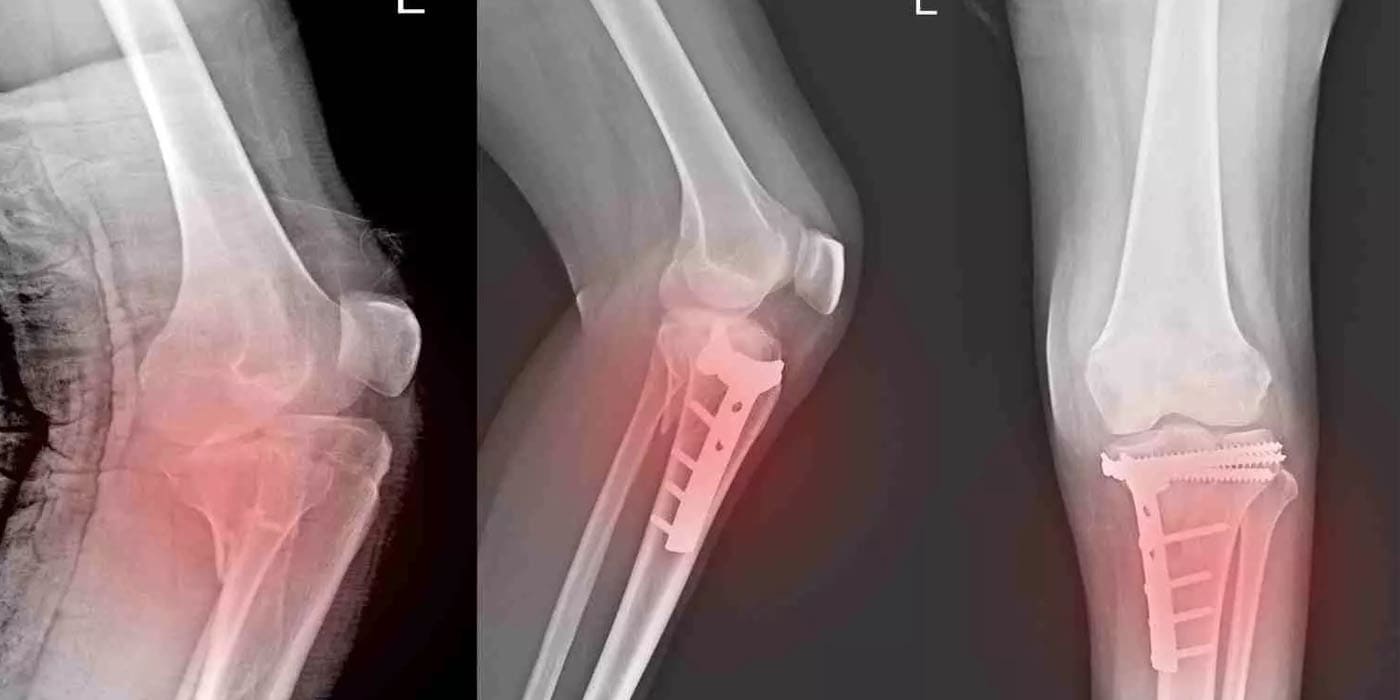

3. Distal Femur Fracture

Occurs at the lower end of the thigh bone, just above the knee. Seen commonly in high-energy trauma or elderly patients with weak bones.

• Open Reduction & Internal Fixation (ORIF)

Using plates, screws, or wires to realign the bone precisely.